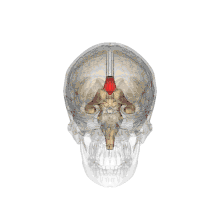

LocationBetween the two brain hemispheres

The corpus callosum (Latin for "tough body"), also callosal commissure, is a wide, thick nerve tract, consisting of a flat bundle of commissural fibers, beneath the cerebral cortex in the brain. The corpus callosum is only found in placental mammals.[1] It spans part of the longitudinal fissure, connecting the left and right cerebral hemispheres, enabling communication between them. It is the largest white matter structure in the human brain, about 10 cm (3.9 in) in length and consisting of 200300 million axonal projections.[2][3]